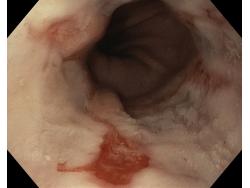

Choroba refluksowa